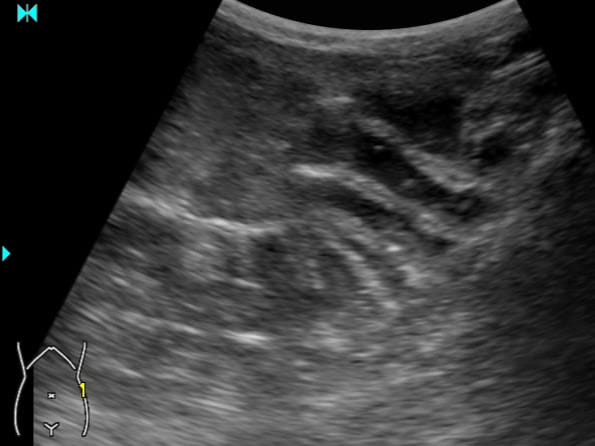

▲爸媽以為孩子便秘肚子痛,但超音波顯示腸胃炎。(圖/臭寶爸 - 兒科陳敬倫醫師授權)

平常排便不順、便秘的孩子得到腸胃炎時,常常只有腹痛(硬便塞著,水便拉不出來),就醫時有時會被當成便秘而被灌腸,甚至還附上軟便藥,回家就開始拉不停.........。照片就是爸媽以為孩子便秘肚子痛,但超音波顯示腸胃炎。

腸胃炎時不用做超音波檢查,但如果孩子有危險徵兆時,超音波可以用來檢查孩子是不是有危急需要盡快處理的問題,如腸套疊、腸阻塞、盲腸炎等等。